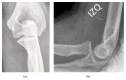

Irreducible Anteromedial Dislocation of Radial Head with Biceps Tendon Interposition

The case presents an isolated irreducible anteromedial dislocation of radial head due to biceps tendon interposition on a 14-year-old female patient. After an unsuccessful closed reduction, a lateral approach of the left elbow was carried out through Kocher's interval. Given that no pathology was found on the radiohumeral joint, the approach was extended distally. This revealed that the biceps tendon was displaced laterally around the radial neck, preventing the reduction. Once the tendon was taken back to its anatomical position, the radial head reduction was performed successfully. The patient achieved a complete functional recovery. Possible injury mechanisms are discussed, as well as the importance of identifying such a rare injury.